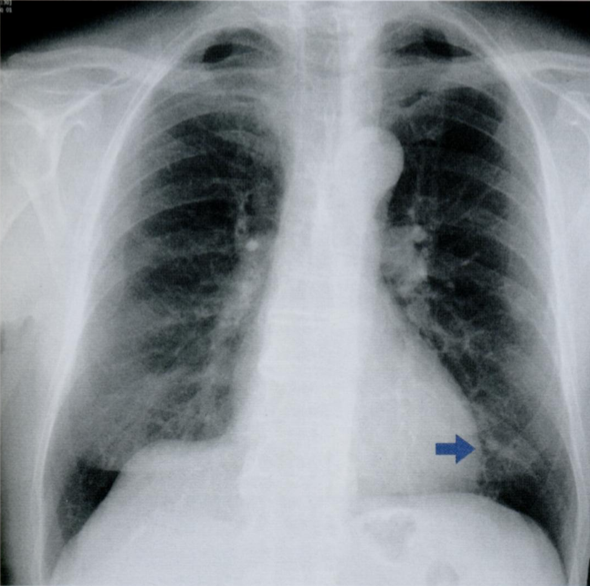

На данной карточке обратите внимание на просветления, отмеченные стрелками, которые свидетельствуют о наличии свободного воздуха в мягких тканях и средостении.

Признаки пневмомедиастинума:

1) эмфизема мягких тканей шеи

2) заметное просветление по контуру сердца или аорты, ограниченное снаружи париетальной плеврой (это то, что видно на данном снимке)

3) субкардиальное или ретрокардиальное скопление воздуха, четкая визуализация диафрагмы на всем протяжении

4) вилочковая железа у детей обнаруживается в виде «треугольного паруса» (у новорожденных - это норма)

5) пневмоторакс

6) пневмоперикард

7) воздух, окружающий ствол легочной артерии (в виде круга в боковой проекции)

На снимках воздух вдоль контуров сердца + воздух между волокон грудных мышц